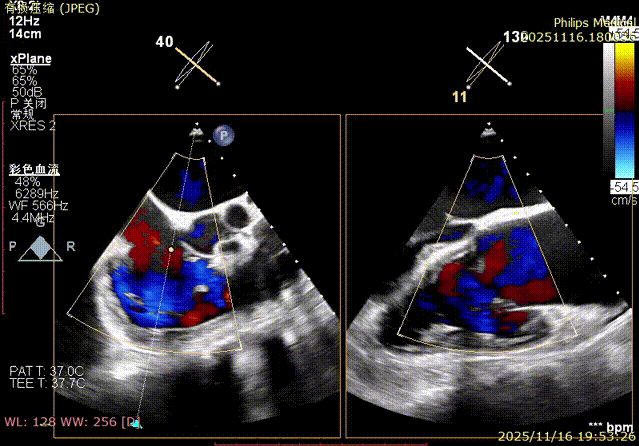

Echocardiographic Assessment: Echocardiography revealed left atrial enlargement. The left atrial appendage (LAA) orifice was 32mm with no thrombus inside. Tricuspid regurgitation was extreme (average vena contracta 18mm). Regurgitant jets were located at the anterior-septal, central, and posterior-septal commissures, with a central gap measuring approximately 13x5.9mm. The annulus was mildly dilated (average diameter 43mm). The tricuspid leaflets showed thickening and degenerative changes.

The entire procedure was guided by both Transesophageal Echocardiography (TEE) and Digital Subtraction Angiography (DSA).

K-Clip® Tricuspid Annuloplasty (Seamless Transition):Immediately after LAAC, the operators established a new vascular access route and advanced the K-Clip® delivery system directly into the right atrium, targeting the posterior-septal and anterior-posterior commissures of the tricuspid annulus. Under real-time ultrasound guidance, the team precisely anchored, clipped, and released the devices.

Immediate intraoperative echocardiographic verification showed that the tricuspid regurgitation area was significantly reduced from a preoperative grade of 5+(pre-op) to 2+(post-op), downgrading the severity from extreme to mild-moderate.

1.Baseline assessment of regurgitation severity.

2.Advancement of the steerable large sheath and delivery system under ultrasound guidance.

3.Steering and rotating the delivery system to target the site while engaging the anchor screw via the 3D MPR plane.

4.Opening the clip arms, adjusting orientation, landing, and closing the clip.